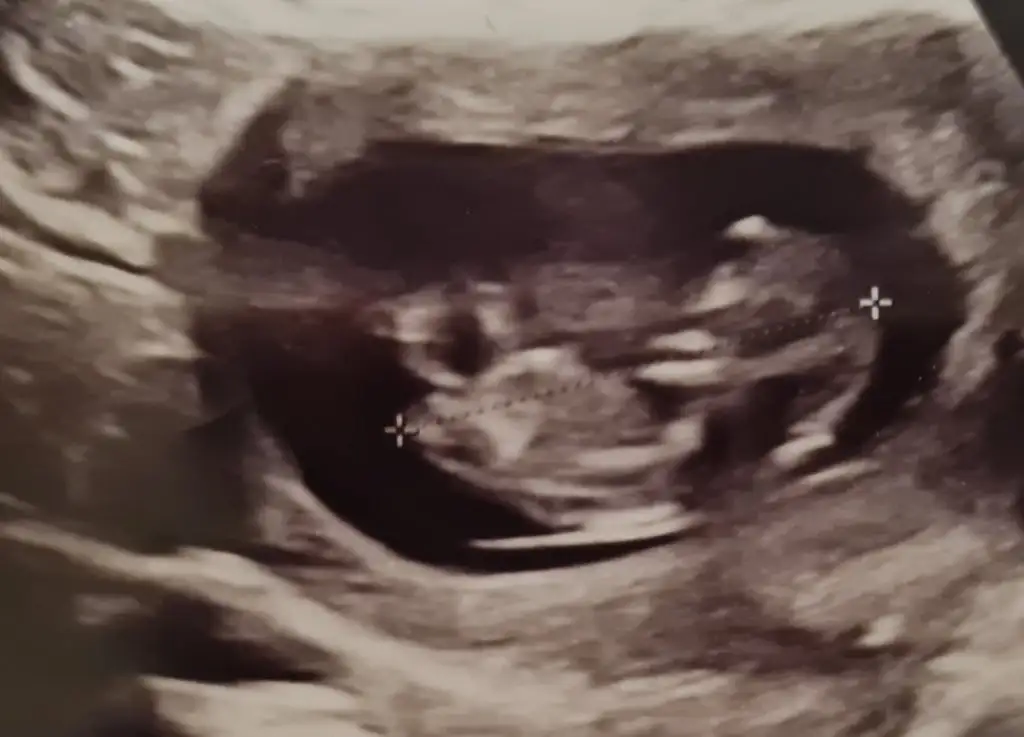

Benimde oluyor ağrılarım ara ara kasıkta ve karnımda. Doktor normal olduğunu söylemişti rahim büyüyor vucudumuz hazırlanıyorKızlar bugün tam 11. Haftaya girdik, bebiş incir büyüklüğündeymiş :) muhtemelen regl tarihim. Kaşıklarımda ince ince ağrılar var. Epeydir olmuyordu. Az korktum. Acaba adet tarihim diye mi ağrım oldu sizde de olmuş muydu ? Yarın doktor kontrolümüz var. Benimle aynı tarihli gele olan arkadaşım vardı. Geçen hafta bebişinin kalbi durmuş kürtaj olmuş ondan mı etkilendim noldu bilmiyorum bugün biraz kaygılıyım sanırım